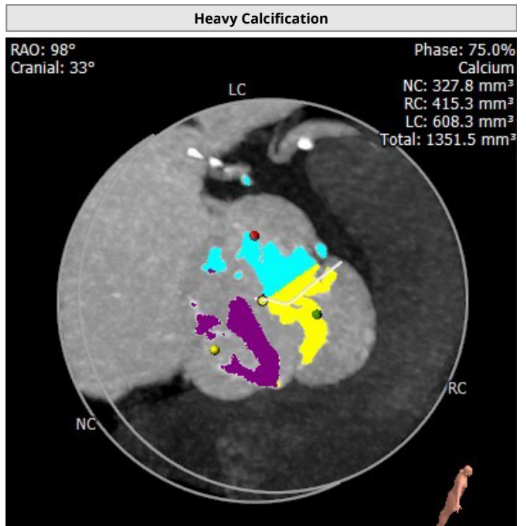

钙化积分及分布

该患者为TYPE1型二叶瓣,且主动脉瓣极重度钙化,钙化积分高达1351,瓣膜移位风险增加。

患者左右窦之间存在钙化融合,融合脊较难推动,且瓣口打开呈椭圆形,可能出现瓣中瓣无法解决的瓣周漏。